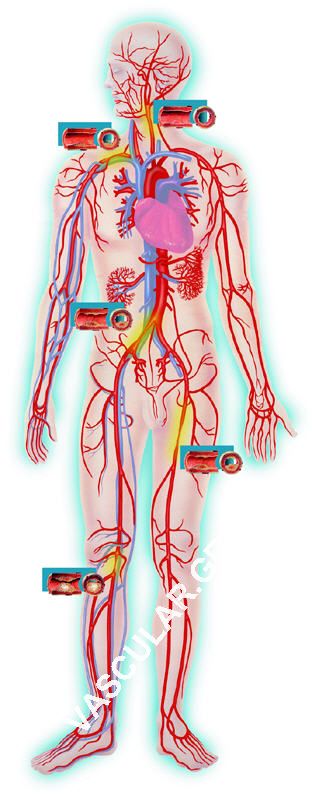

Yðåñç÷çôéêÞ Ðáíáñôçñéïãñáößá, áðïôåëåß ôçí åîÝôáóç ôùí áñôçñéþí ïëïêëÞñïõ ôïõ áíèñùðßíïõ óþìáôïò äé’õðåñç÷ùí. êáé ôçò Duplex/Ôriplex åîåôÜóåùò áíþäõíá, áíáßìáêôá ÷ùñßò ôçí ðáñáìïíÞ ôïõ áóèåíïýò óôï Íïóïêïìåßï

Ç " Õðåñç÷çôéêÞ ðáíáñôçñéïãñáößá" (Õ.Ð) åßíáé Ýíá óýíïëï åîåôÜóåùí ðïõ ðåñéëáìâÜíåé:

á. Ôïí Ýëåã÷ï ôùí åíäïêñáíéáêþí áñôçñéáêþí óôåëå÷þí äçëáäÞ ðñïóèßá -ìÝóç-ïðéóèßá êáé âáóéêÞ åãêåöáëéêÞ áñôçñßá.

â. Ôïí Ýëåã÷ï ôùí åîùêñáíéáêþí áñôçñéáêþí óôåëå÷þí ôïõ ôñá÷Þëïõ äçëáäÞ êïéíÞò -Ýîù-Ýóù êáñùôßäïò êáé óðïíäõëéêÞò áñôçñßáò.

ã. Ôïí Ýëåã÷ï ôçò êïéëéáêÞò áïñôÞò , äé÷áóìïý ôçò êïéëéáêÞò áïñôÞò, ëáãïíßùí áñôçñéþí, ìçñéáßùí êáé éãíõáêþí áñôçñéþí.

ä. Ôïí õðïëïãéóìü äåßêôïõ ðéÝóåùò óöõñþí (ÄÐ) ðïõ åßíáé ï ëüãïò ôçò áñôçñéáêÞò ðéÝóåùò ôçò ñá÷éáßáò ôïõ ðïäüò áñôçñßáò ( Ä.Ð .Ñ.Ð) Þ ïðéóèßáò êíçìéáßáò áñôçñßáò (Ä.Ð.Ï.Ê) ðñïò ôçí óõóôçìáôéêÞ áñôçñéáêÞ ðßåóç ôçò âñá÷éïíßïõ áñôçñßáò.

å. Ôïí Ýëåã÷ï ôùí áñôçñéþí ôïõ ðÝïõò Þôïé ÄÅ êáé ÁÑ ñá÷éáßáò áñôçñßáò ôïõ ðÝïõò êáé ôùí åí ôù âÜèåé áñôçñéþí ôïõ ðÝïõò óôïí áíäñéêü öõóéêÜ ðëçèõóìü